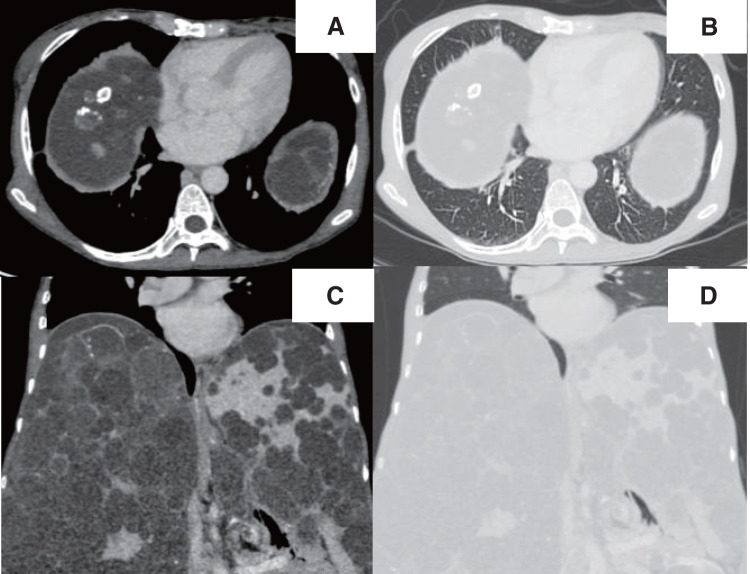

Case presentation: A 57-year-old woman with a diagnosis of autosomal dominant polycystic kidney disease underwent deceased-donor liver transplantation for polycystic liver disease. She did not have any background lung disease, although her right lower lobe was mostly atelectatic due to a remarkably elevated diaphragm. The liver transplant itself was uneventful. A small hole was made in the right diaphragm during the dissection of the liver, but it was successfully repaired without any injury to the lung. On postoperative day 1, the chest radiograph revealed a round hypertranslucency on the right side, which was initially considered subphrenic air retention, and no further evaluation was made at that time. Given that the hypertranslucency persisted, follow-up computed tomography was performed on postoperative day 18, and revealed an air-fluid level above the diaphragm in the right thoracic cavity. Thoracoscopic investigation revealed an intrathoracic hematoma within a pneumatocele in the right lower lobe, which was not detected in the pretransplant computed tomography. The hematoma was removed, and the pneumatocele was resected.